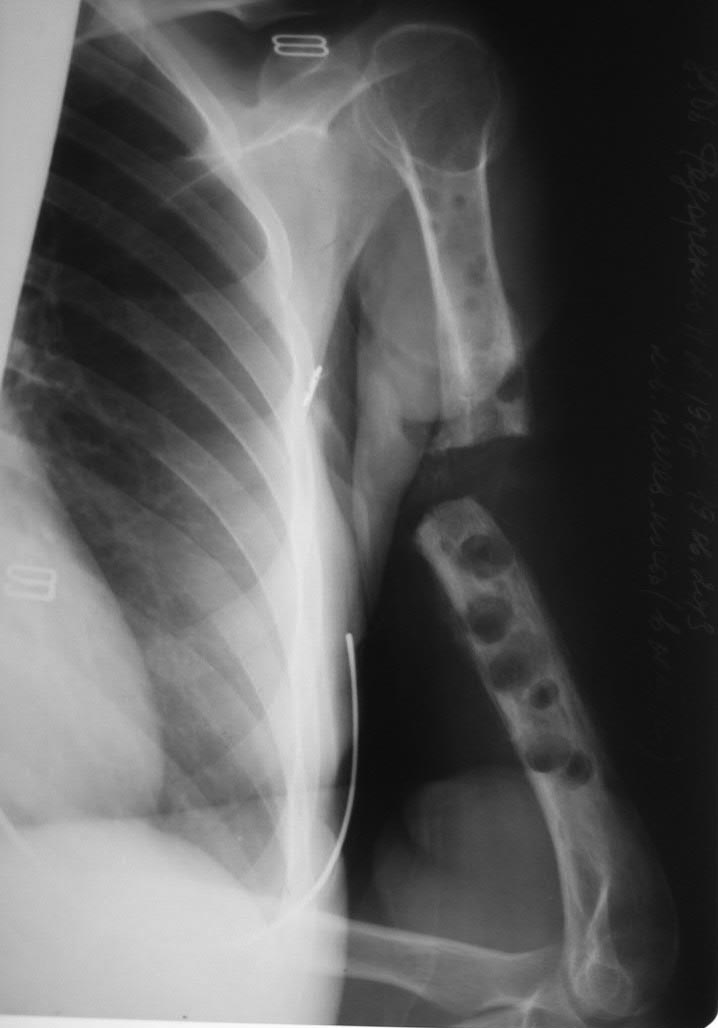

дефект-диастаз левой плечевой кости

Сейчас - дефект-диастаз+укорочение. Суммарный дефект около 6 см. Дырки от винтов. Инфекции нет.

Что делать сейчас - вариантов много. Надо ли восстанавливать длину? Как насчет аппарата? Этот вариант выглядит не самым простым, уж больно издырявлено все.

Плечо неплохо перенесит укорочение до 3 см, а дефект 6 см лучше заместить. Метод удлинения по Илизарову длителен и трудоемок, а остальные методы без открывания очага не получатся. Возможно, множественные операции повлияли на состояние мягких тканей, и если условия позволяют, тогда я бы поставил гвоздь с титановым или любым другим кейджем. Трубка-кейдж ограничит аутокость изнутри и создаст стабильность после блокировки.